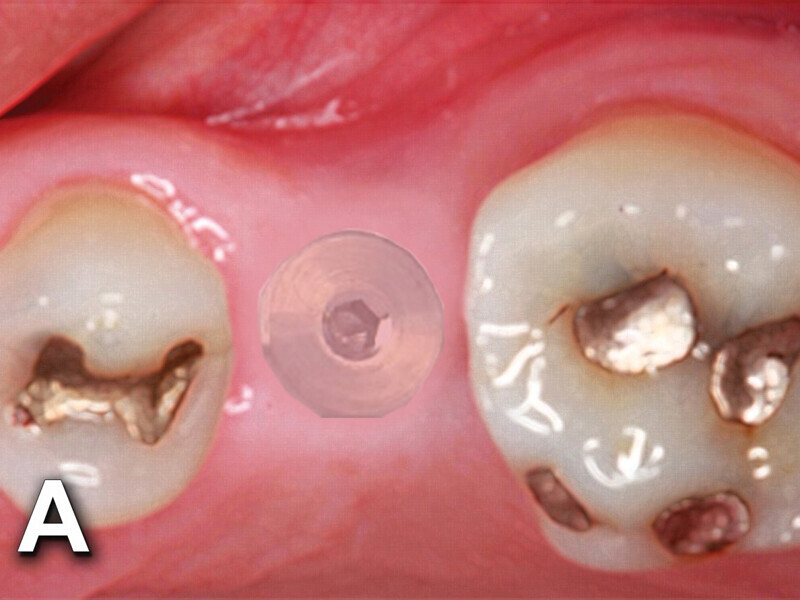

Fig. 4b: Implant to be uncovered (4a) presents with two options depending on width of attached gingiva available. Wide band of attached gingiva will remain after removal of tissue over cover screw, and the diode is utilized in a spiral pattern starting at center until fully exposed (4b). With the narrow band of attached gingiva present, an elliptical cut is made with the diode and tissue is pushed buccally and lingually to preserve the attached gingiva (4c). (Photo provided by Dr. Gregori M. Kurtzman)